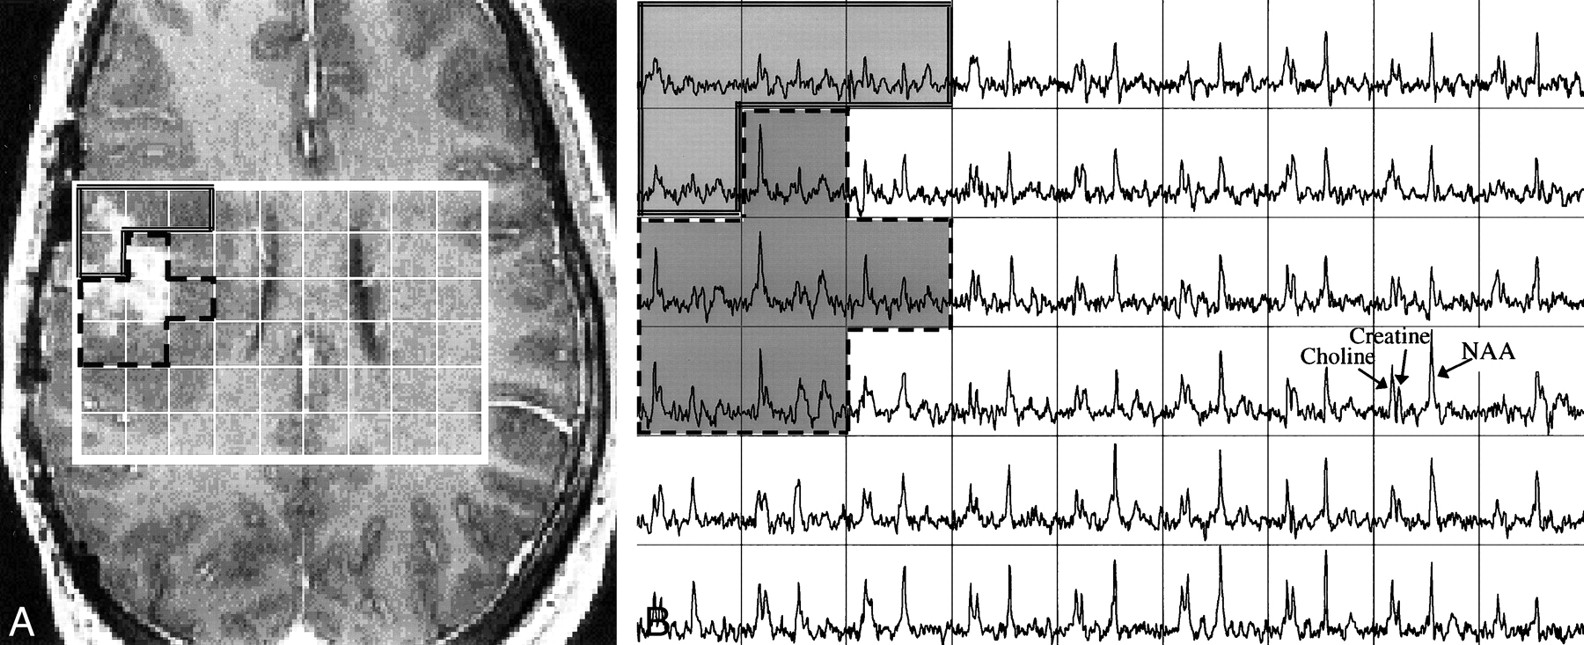

Although the spectra from normal-appearing brain tissue were similar in terms of their choline, creatine, and NAA levels, spectra from the mass lesions all showed a reduction in the NAA resonance, and many showed an elevation in the choline resonance. This is illustrated by the case of oligoastrocytoma, shown in Figure 2, wherein a contiguous region of six voxels had spectra with these characteristics.

A, Axial image from a contrast-enhanced SPGR 3D volume dataset (34/3/1) of a patient with an oligoastrocytoma. The locations for which spectra are reconstructed are shown by the grid.

B, Spectral array (16 × 8 × 8 [phase encodes], 1000/144/1) corresponding to the grid shown in the image of A. Note the high NAA levels and moderate choline and creatine levels in the spectra corresponding to the normal MR regions (right side of spectral array). Note the very high choline and low NAA in portions of the contrast enhancement and surrounding tissue (dashed lines) and the lower metabolites in adjacent tissue (double lines).